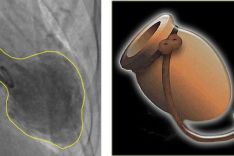

It is thought that at least 3,000 adults in the UK a year suffer from ‘broken heart syndrome’ – or takotsubo – but the true number may be even higher.

A new study reveals that the "broken heart syndrome" or also referred to as takotsubo syndrome may have longer-lasting damaging effects on the heart. Until now, it was thought the heart fully recovered from the syndrome, but new research suggests the muscle actually suffers long-term damage.